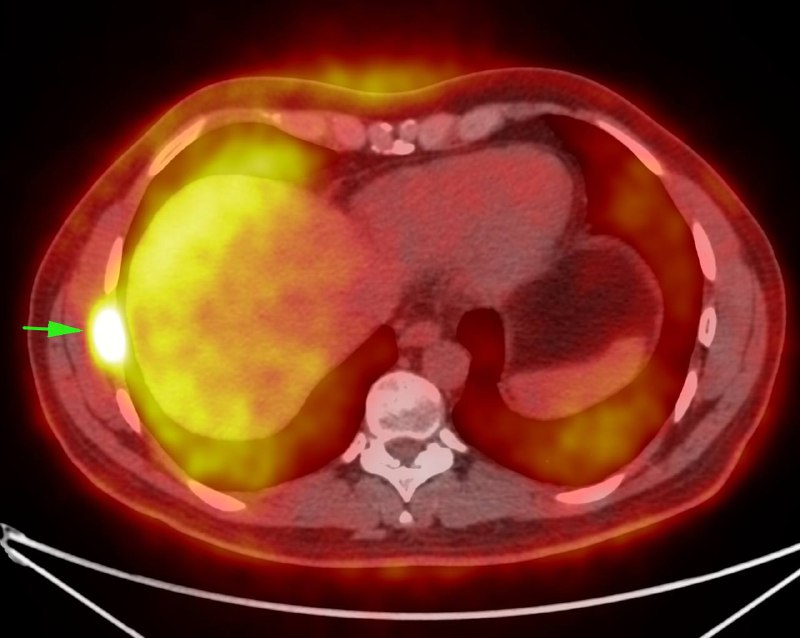

Инфекции желчевыводящих путей могут быть вызваны внутренними причинами (холецистит, соустья из-за камней, опухолей, изьязвлений с пенетрациями), а также осложнять вмешательства (рефлюкс-холангит после анастомозов, дренирующих вмешательств, реконструкций протоков, литоэкстракций). Диагноз холангита, в основном, клинический, но могут развиваться и видимые нам проявления: газ в протоках, структурные изменения печени, абсцессы.